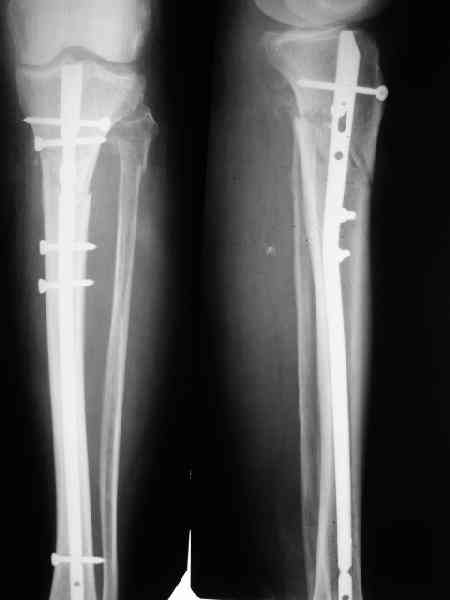

В приложении как раз видна эволюция использововшихся у нас большеберцовых гвоздей. Первый - дизайн как у UTN, второй - разнесены 45 градусные отверстия (зачем их вообще изначально так нелепо на одном уровне сделалм???), третий - убрано сиавшее лишним статическое отверстие, Herzog's bend перемещен более проксимально.

Забавненько смотрится... "век живи, век учись", как говорится. А чья мысль использовать блокируемые штифты для б/берцовой кости при переломах бедра? Такое встречалось где-то в литературе или это ваше ноу-хау?